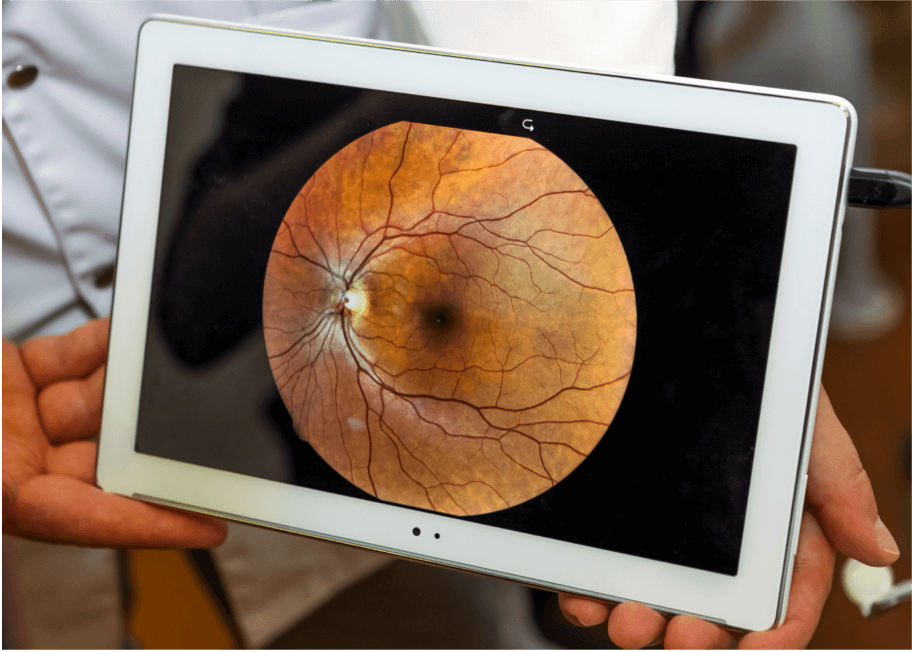

Retinografia do fundo ocular

Isso é feito usando um microscópio de baixa potência para obter imagens coloridas da retina. É bastante usada no diagnóstico de DMRI, pois mostra anormalidades como drusas, alterações pigmentares (cor), atrofia, sangramento e acúmulo de líquidos. As imagens obtidas ao longo do tempo podem ser comparadas para monitorar a progressão da doença.2